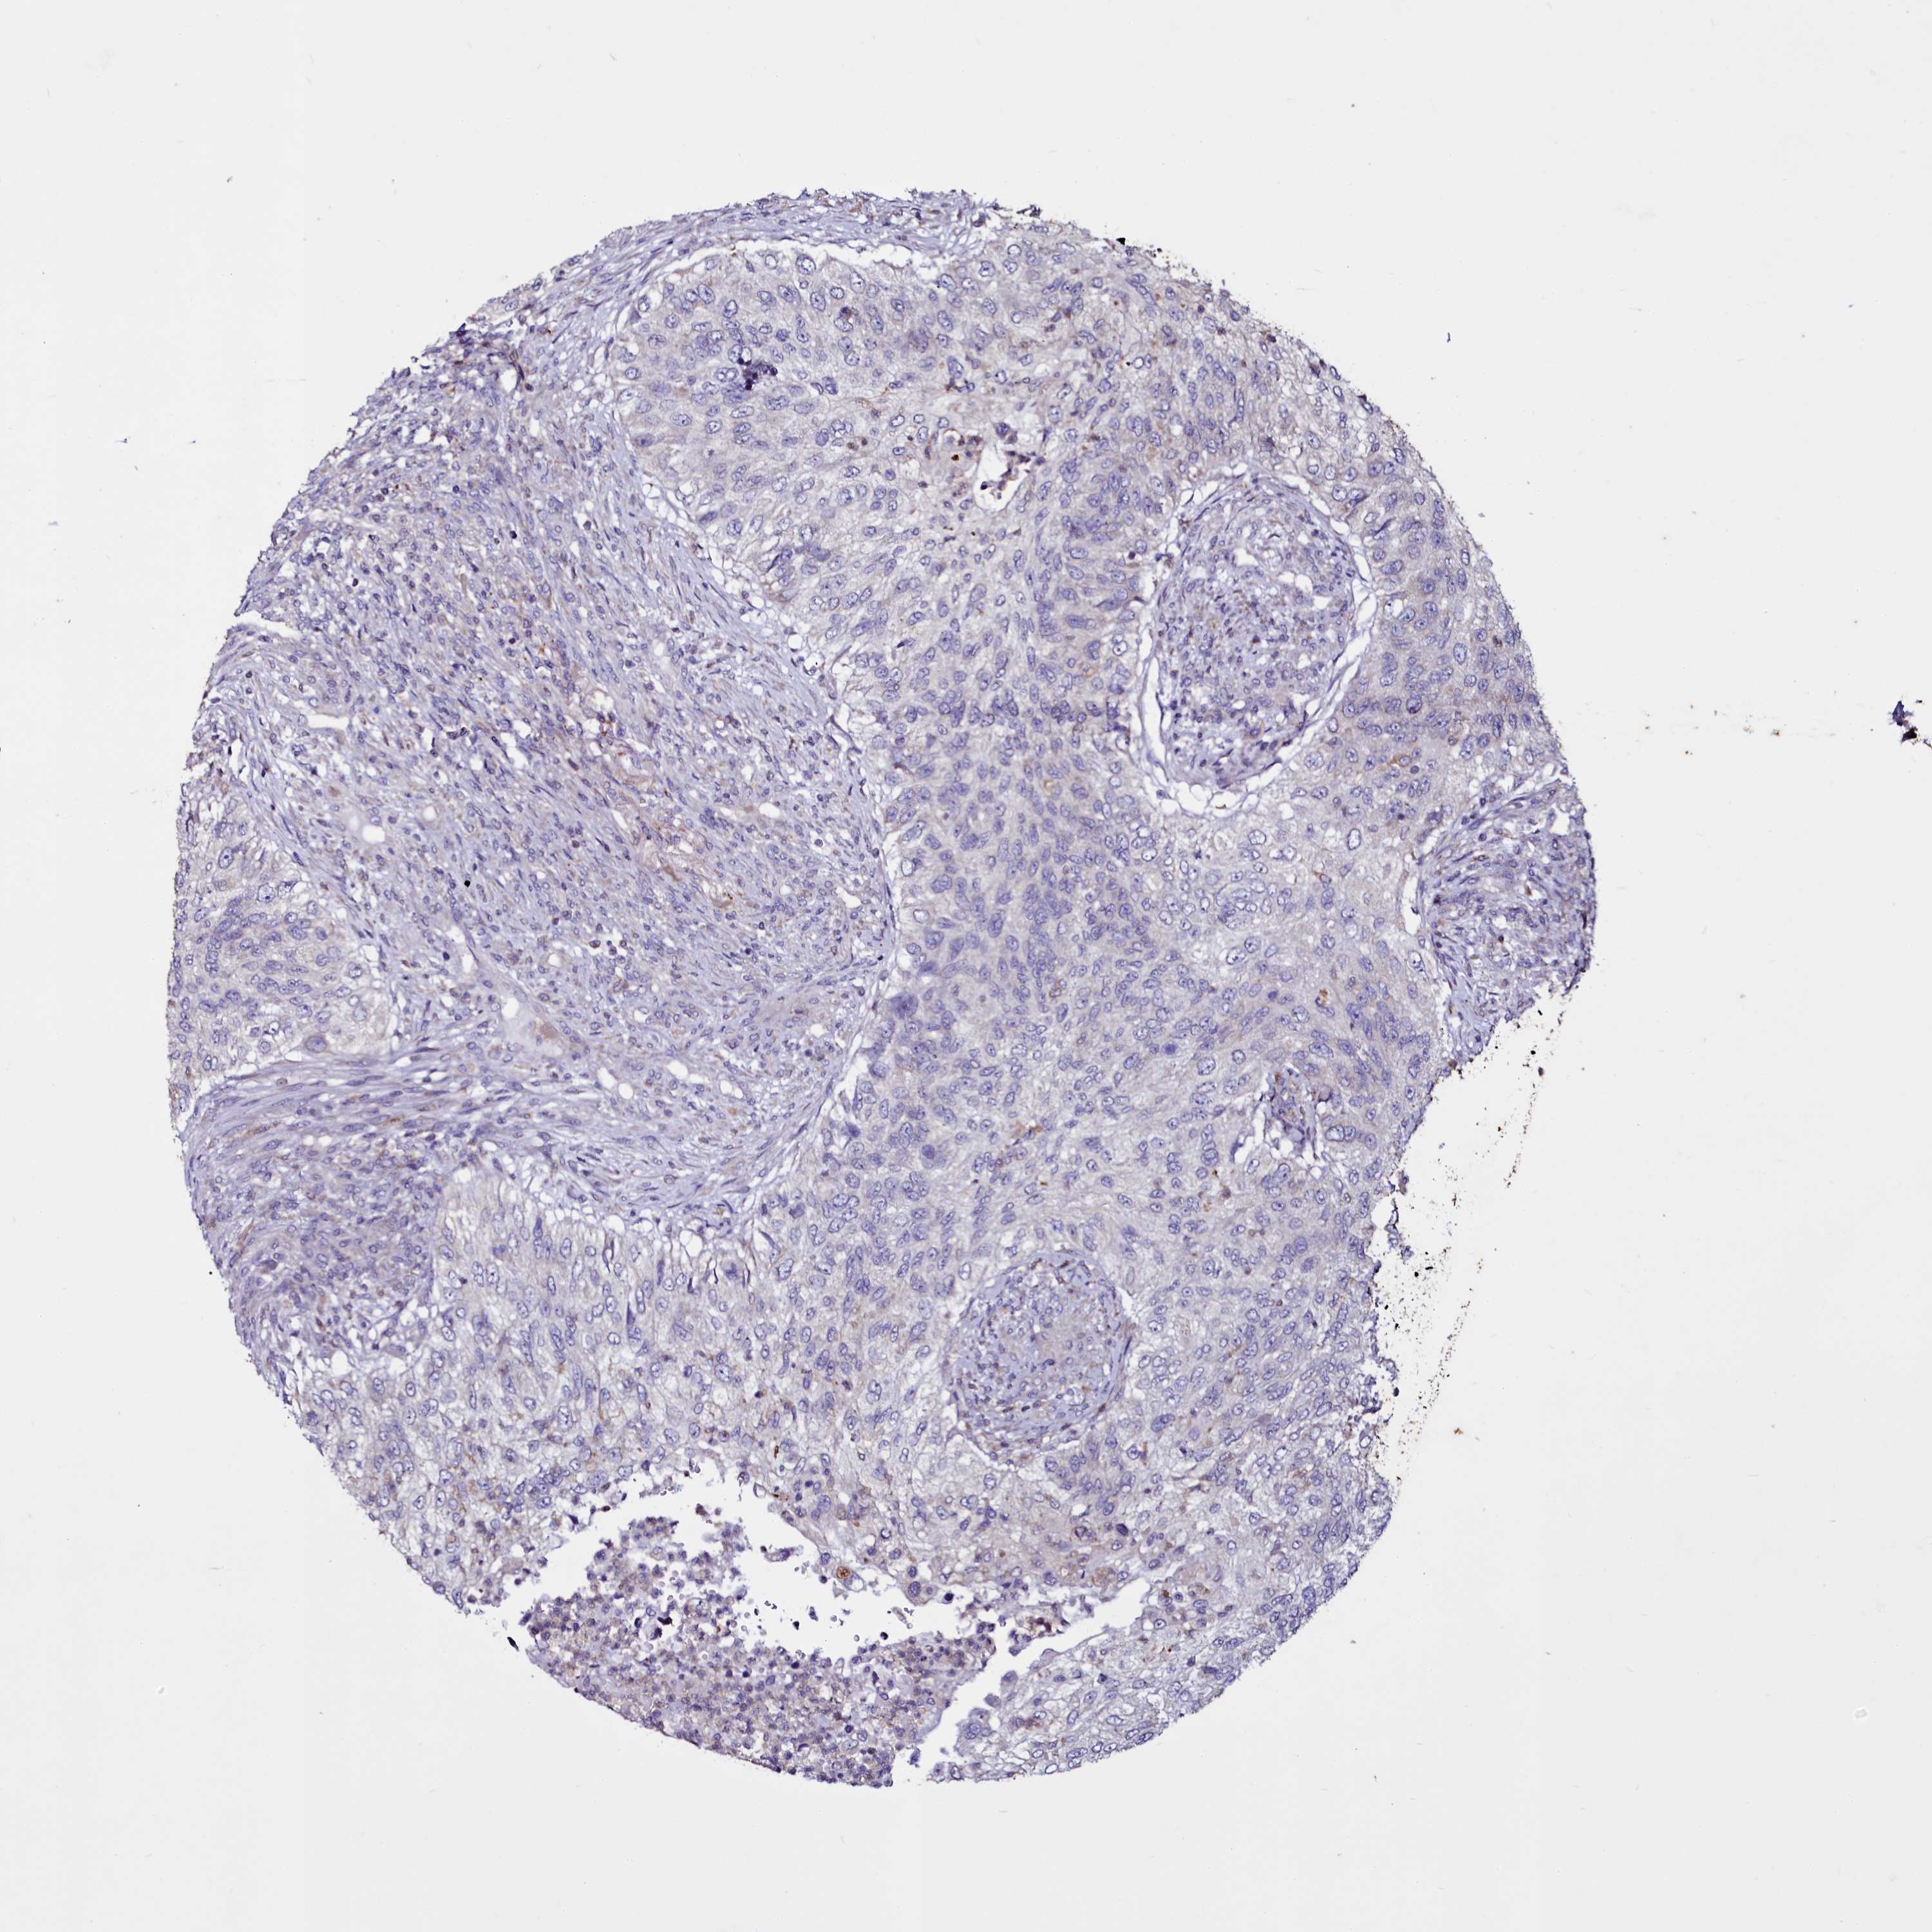

UROTHELIAL CANCER - Protein expressioni

A mouse-over function shows sample information and annotation data. Click on an image to view it in a full screen mode. Samples can be filtered based on level of antibody staining by selecting one or several of the following categories: high, medium, low and not detected. The assay and annotation is described here.

Note that samples used for immunohistochemistry by the Human Protein Atlas do not correspond to samples in the TCGA dataset.

Antibody stainingi

Antibody staining in the annotated cell types in the current human tissue is reported as not detected, low, medium, or high, based on conventional immunohistochemistry profiling in selected tissues. This score is based on the combination of the staining intensity and fraction of stained cells.

Each image is clickable and will lead to virtual microscopy that enables deeper exploration of all samples and also displays staining intensity scores, fraction scores and subcellular localization as well as patient and tissue information for each sample.

Antibody HPA039780

Staining

High

Medium

Low

Not detected

Intensity

Strong

Moderate

Weak

Negative

Quantity

>75%

75%-25%

<25%

None

Location

Nuclear

Cytoplasmic/membranous

Cytoplasmic/membranous,nuclear

Urothelial carcinoma, High grade

Urothelial carcinoma, Low grade